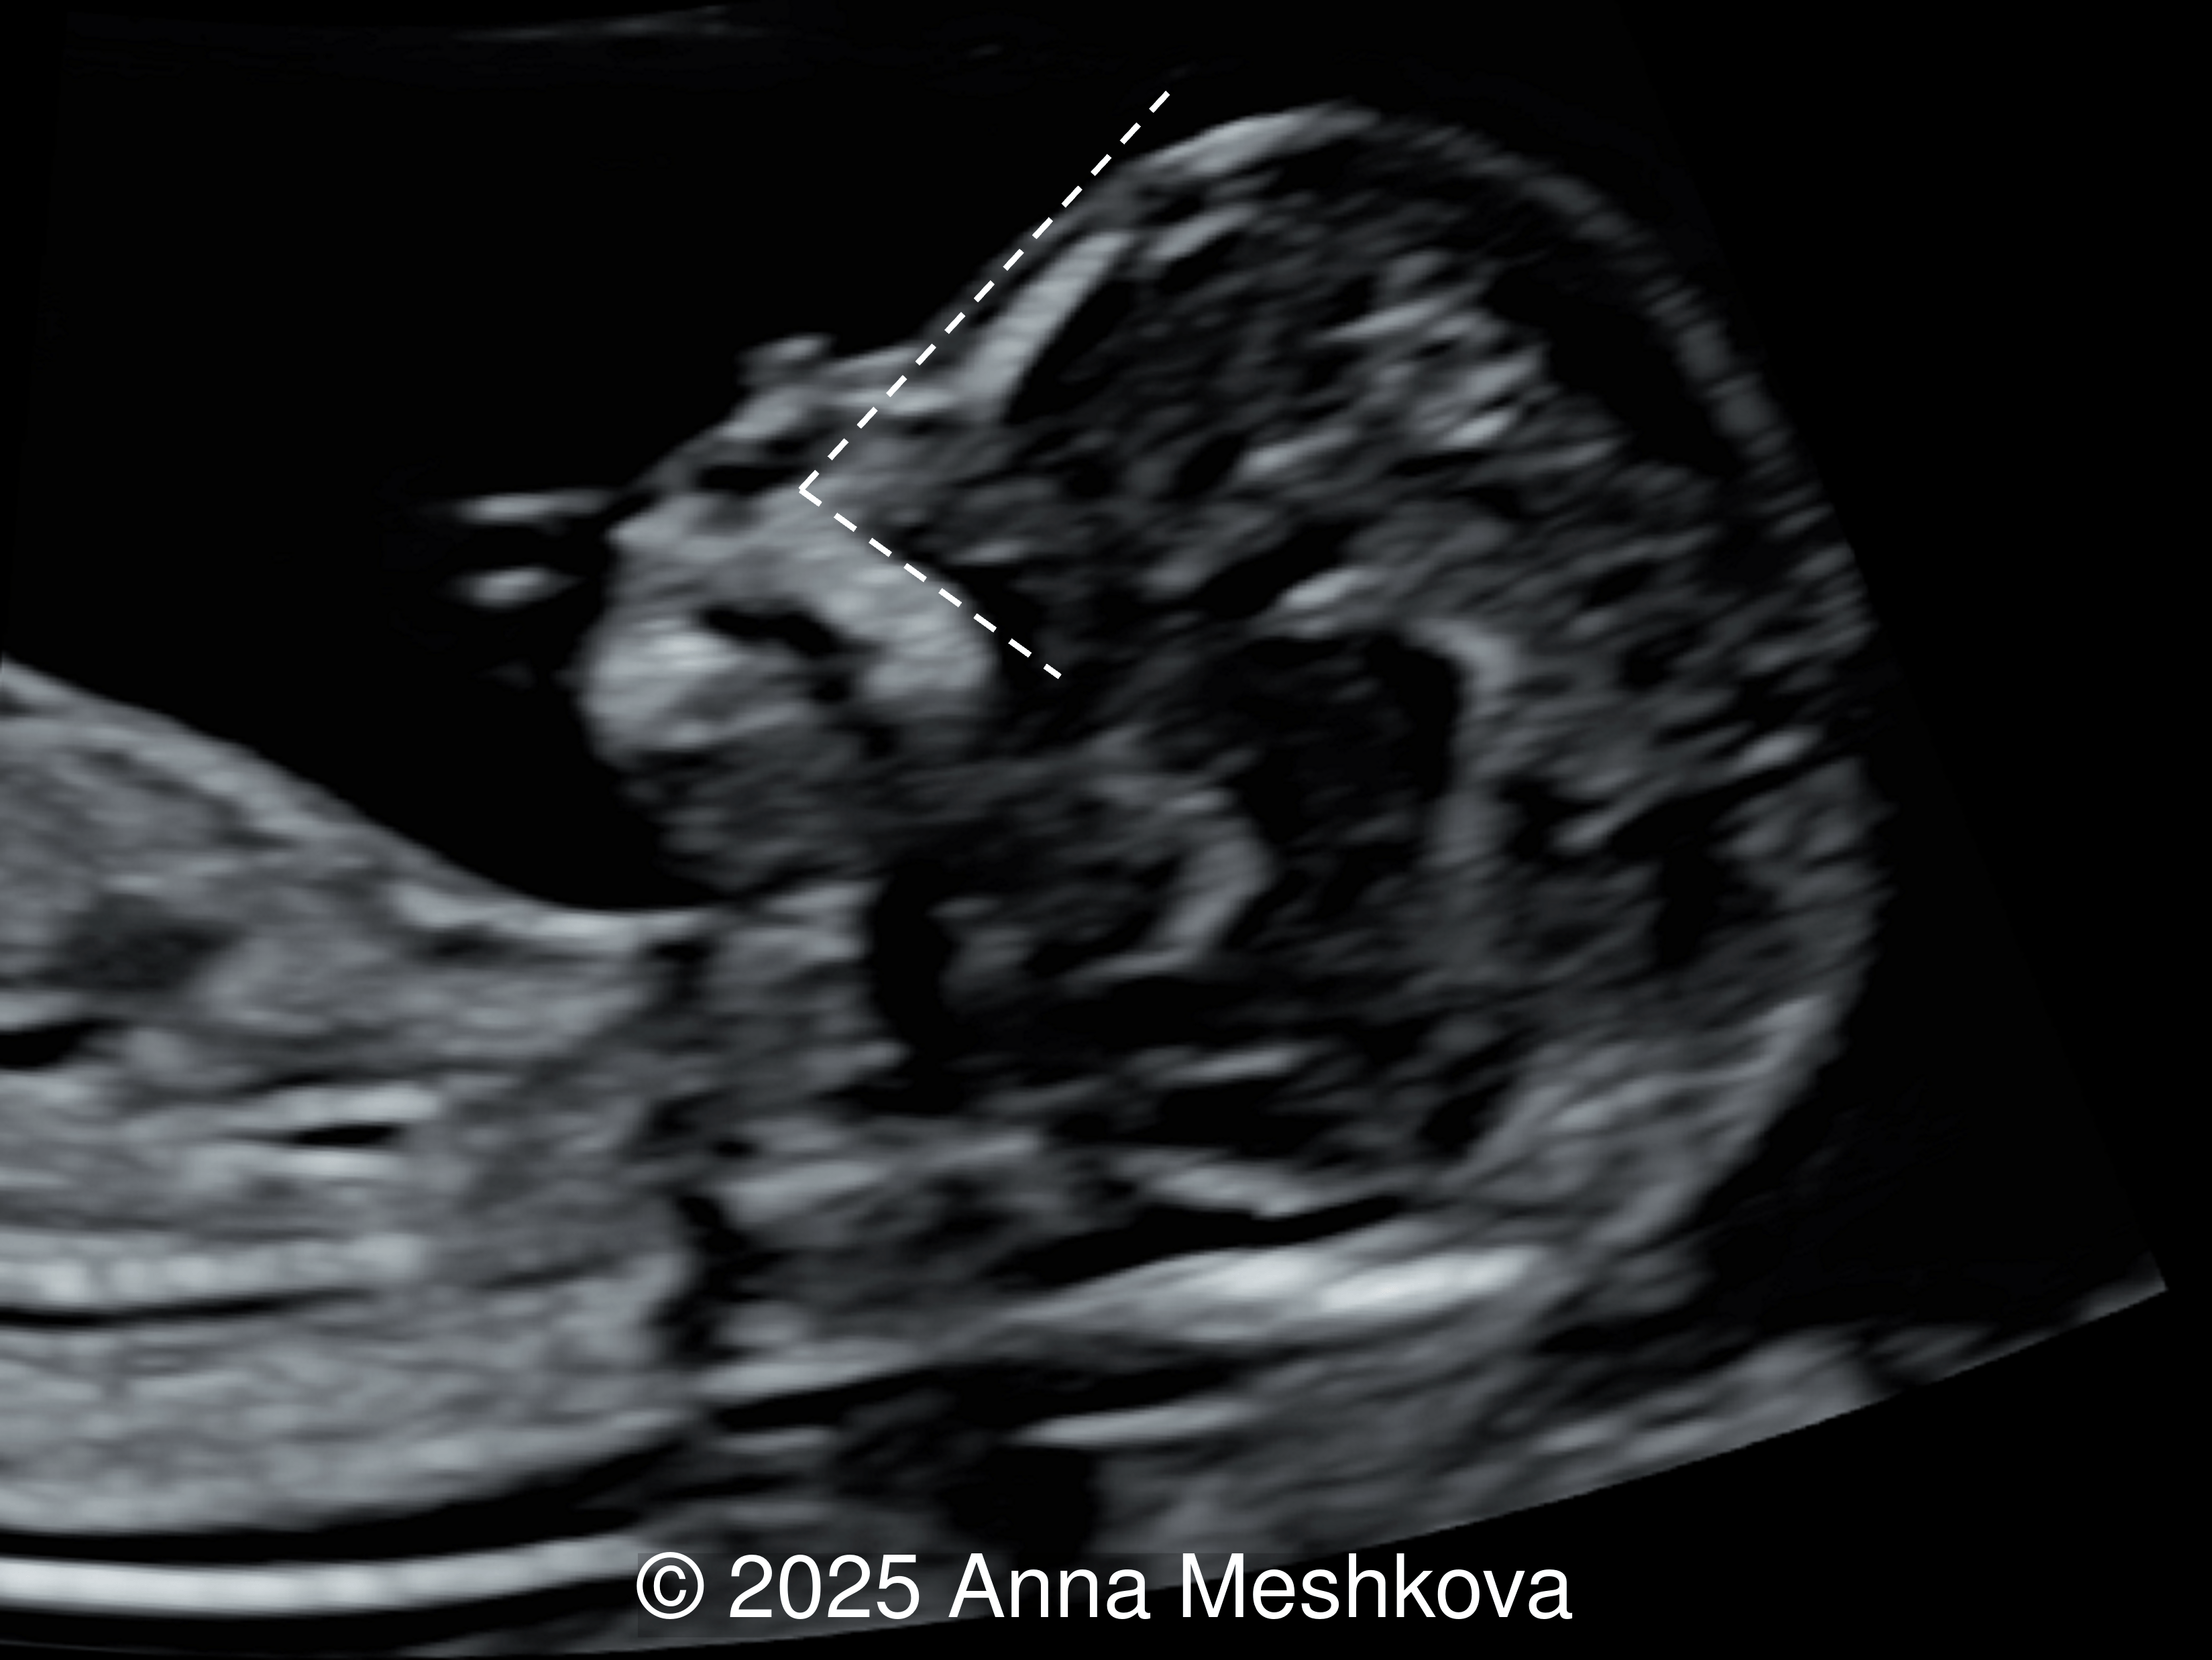

• Image 3, Video 1: Mid-sagittal image demonstrating the mid brain and brain stem displaced posteriorly, known as the "crash" sign. Intracranial translucency is difficult to visualize.